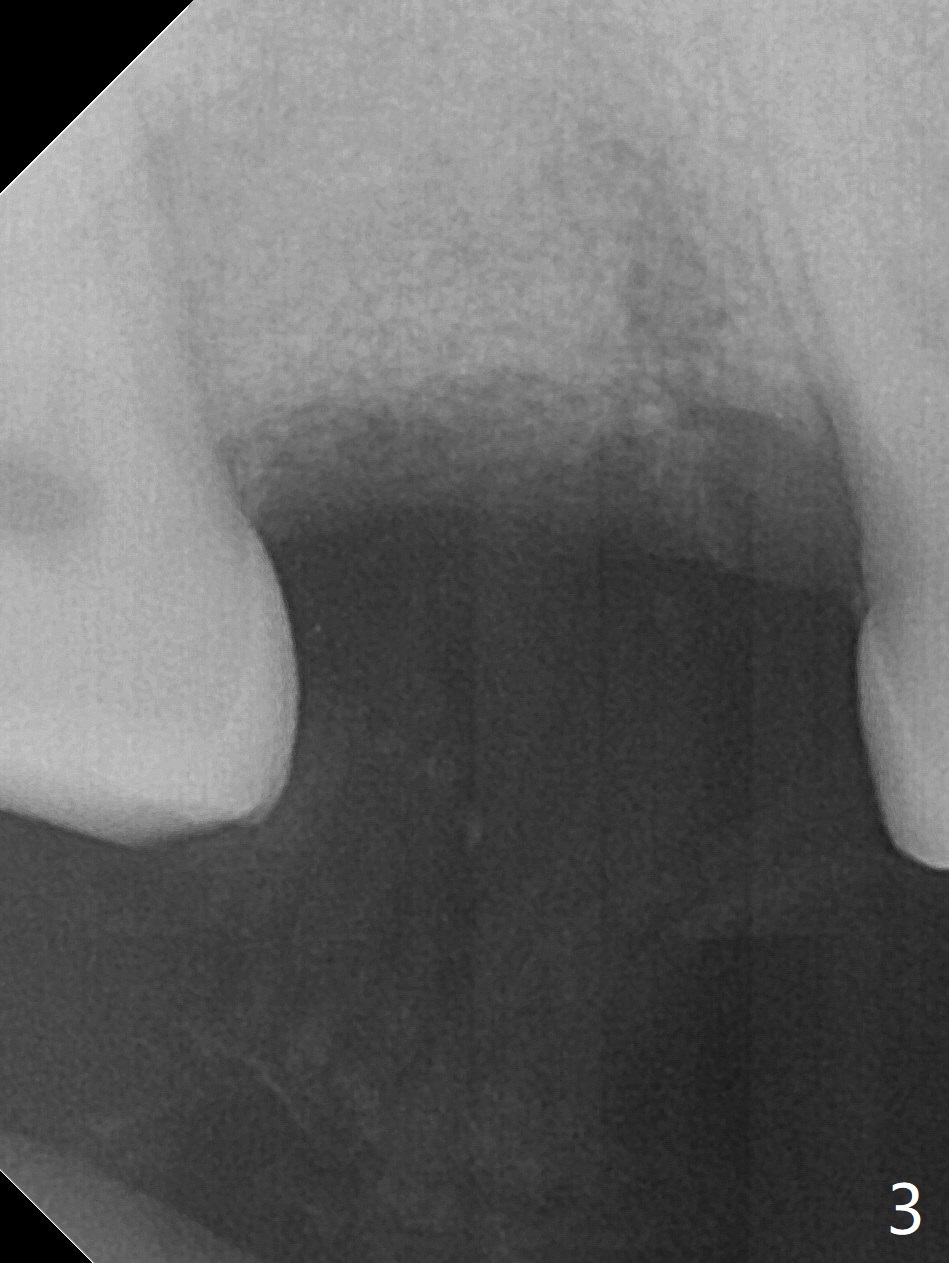

Not long postop, the patient called saying that #2 provisional had dislodged. Due to his busy schedule and coronavirus outbreak, he returns nearly 4 months postop. The abutment is distalized and loose with the underlying implant (5x9 mm). The latter is removed before local anesthesia (Fig.1 distal defect). After initial debridement, a 2.2x13 mm drill is used with a guide of 12 mm offset, followed by insertion of a 4.5x11 mm dummy implant with barely stability (Fig.2). A 5.5x9 mm is placed free hand initially, followed by guide with stability. But the implant has uncovered threads distolingual. Thorough debridement reveals that the sinus membrane has a small perforation. After placement of a piece of Osteogen plug, cortical chip and Vanilla hydrated with .25 cc of GEM21S is packed into the site with a condenser (Fig.3,4). The graft is fixed in place with Perio glue, followed by a piece of GEM Cap with the glue. Three to 4 months later, take CT for healing confirmation. Try to place a shorter implant (e.g., 5x7 mm) without getting into the sinus to reduce infection. In fact the Cap does not stay in place with loss of bone graft (8 days postop).